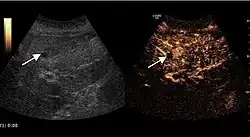

It is the most common liver tumor with a prevalence of 0.4 – 7.4%. It is generally asymptomatic but also can be associated with pain complaints or cytopenia and/or anemia when it is very bulky. It is unique or paucilocular. It can be associated with other types of benign liver tumors. Characteristic 2D ultrasound appearance is that of a very well defined lesion, with sizes of 2–3 cm or less, showing increased echogenity and, when located in contact with the diaphragm, a "mirror image" phenomenon can be seen. When palpating the liver with the transducer the hemangioma is compressible sending reverberations backwards. Doppler exploration reveals no circulatory signal due to very slow flow speed. CEUS investigation has real diagnosis value due to the typical behavior of progressive CA enhancement of the tumor from the periphery towards the center. The enhancement is slow, during several minutes, depending on the size of hemangioma and on the presence (or absence) of internal thrombosis. During late (sinusoidal) phase, if totally "filled" with CA, hemangioma appears isoechoic to the liver. Deviations from the above described behavior can occur in arterialized hemangiomas or those containing arterio-venous shunts. In these cases, differentiation from a malignant tumor is difficult and requires other imaging procedures, follow up and measurements of the tumor at short time intervals.[4]